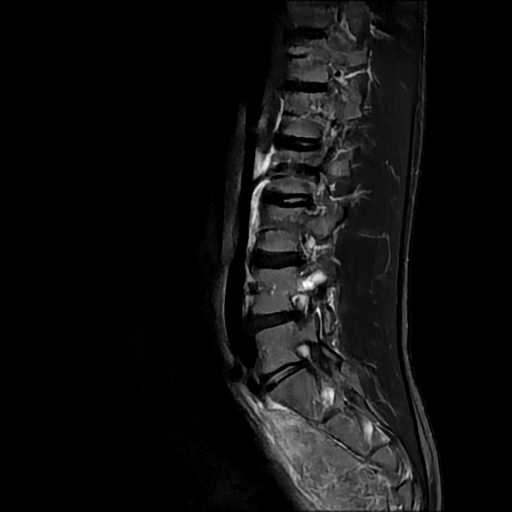

MRI検査

整形外科領域

脊椎

椎間板ヘルニア

圧迫骨折

分離症